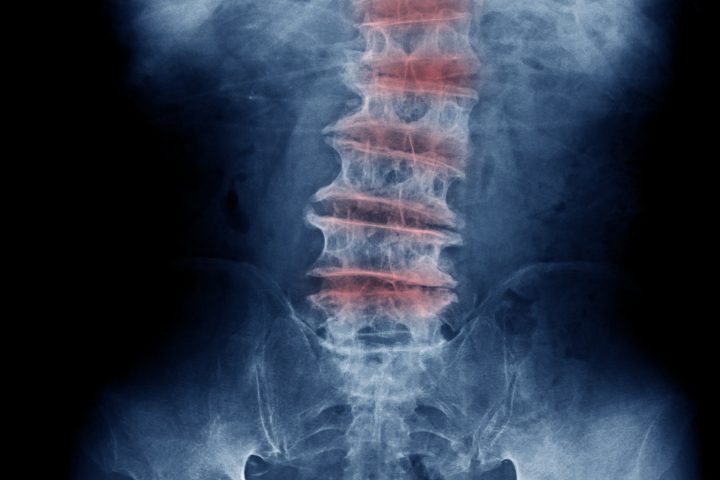

Degenerative Disc Disease Explained!

Degenerative Disc Disease (D.D.D) is one of the most common causes of low back and neck pain and also one of the most misunderstood! The term “degenerative” implies that the symptoms will get worse with age. However the term does not refer to the symptoms, but rather describes the process of the disc degenerating over […]